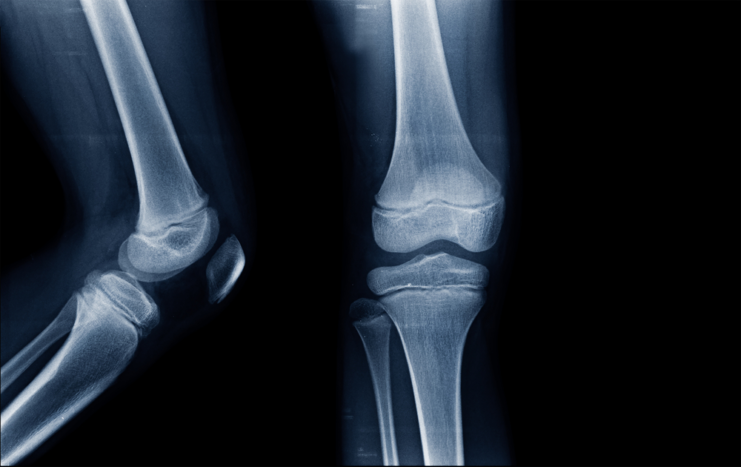

အရိုးနုဆိုတာ ခန္ဓါကိုယ်အတွက် မရှိမဖြစ်အရေးပါတဲ့ အစိတ်အပိုင်းတွေထဲက တစ်ခုပါ။ တွယ်ဆက်တစ်ရှုးလို့ သိထားကြပြီး ခန္ဓါကိုယ်နေရာအနှံ့မှာရှိနေနိုင် ပါတယ်။ အရိုးနုလေးတွေ ကျန်းမာ ကောင်းမွန်နေလို့သာ ကိုယ်ခန္ဓါအစိတ်အပိုင်းတွေကို လိုသလို အကွေးအဆန့်လုပ်ပြီး လှုပ်ရှားနိုင်နေတာပါ။

တကယ်လို့ အရိုးနုလေးတွေသာထိခိုက်ပျက်စီးသွားမယ်ဆိုရင်ရောင်ရမ်းနာကျင်တာ၊ အကြောတွေ တင်းတောင့်နေတာ၊ နာကျင်တာတွေခံစားရနိုင်ပါတယ်။ ဒီအခြေအနေကနောက်ပိုင်းမှာ အဆစ်အမြစ်တွေရာင်ရမ်းနာကျင်တာမျိုးအထိဖြစ်စေနိုင်ပါတယ်။